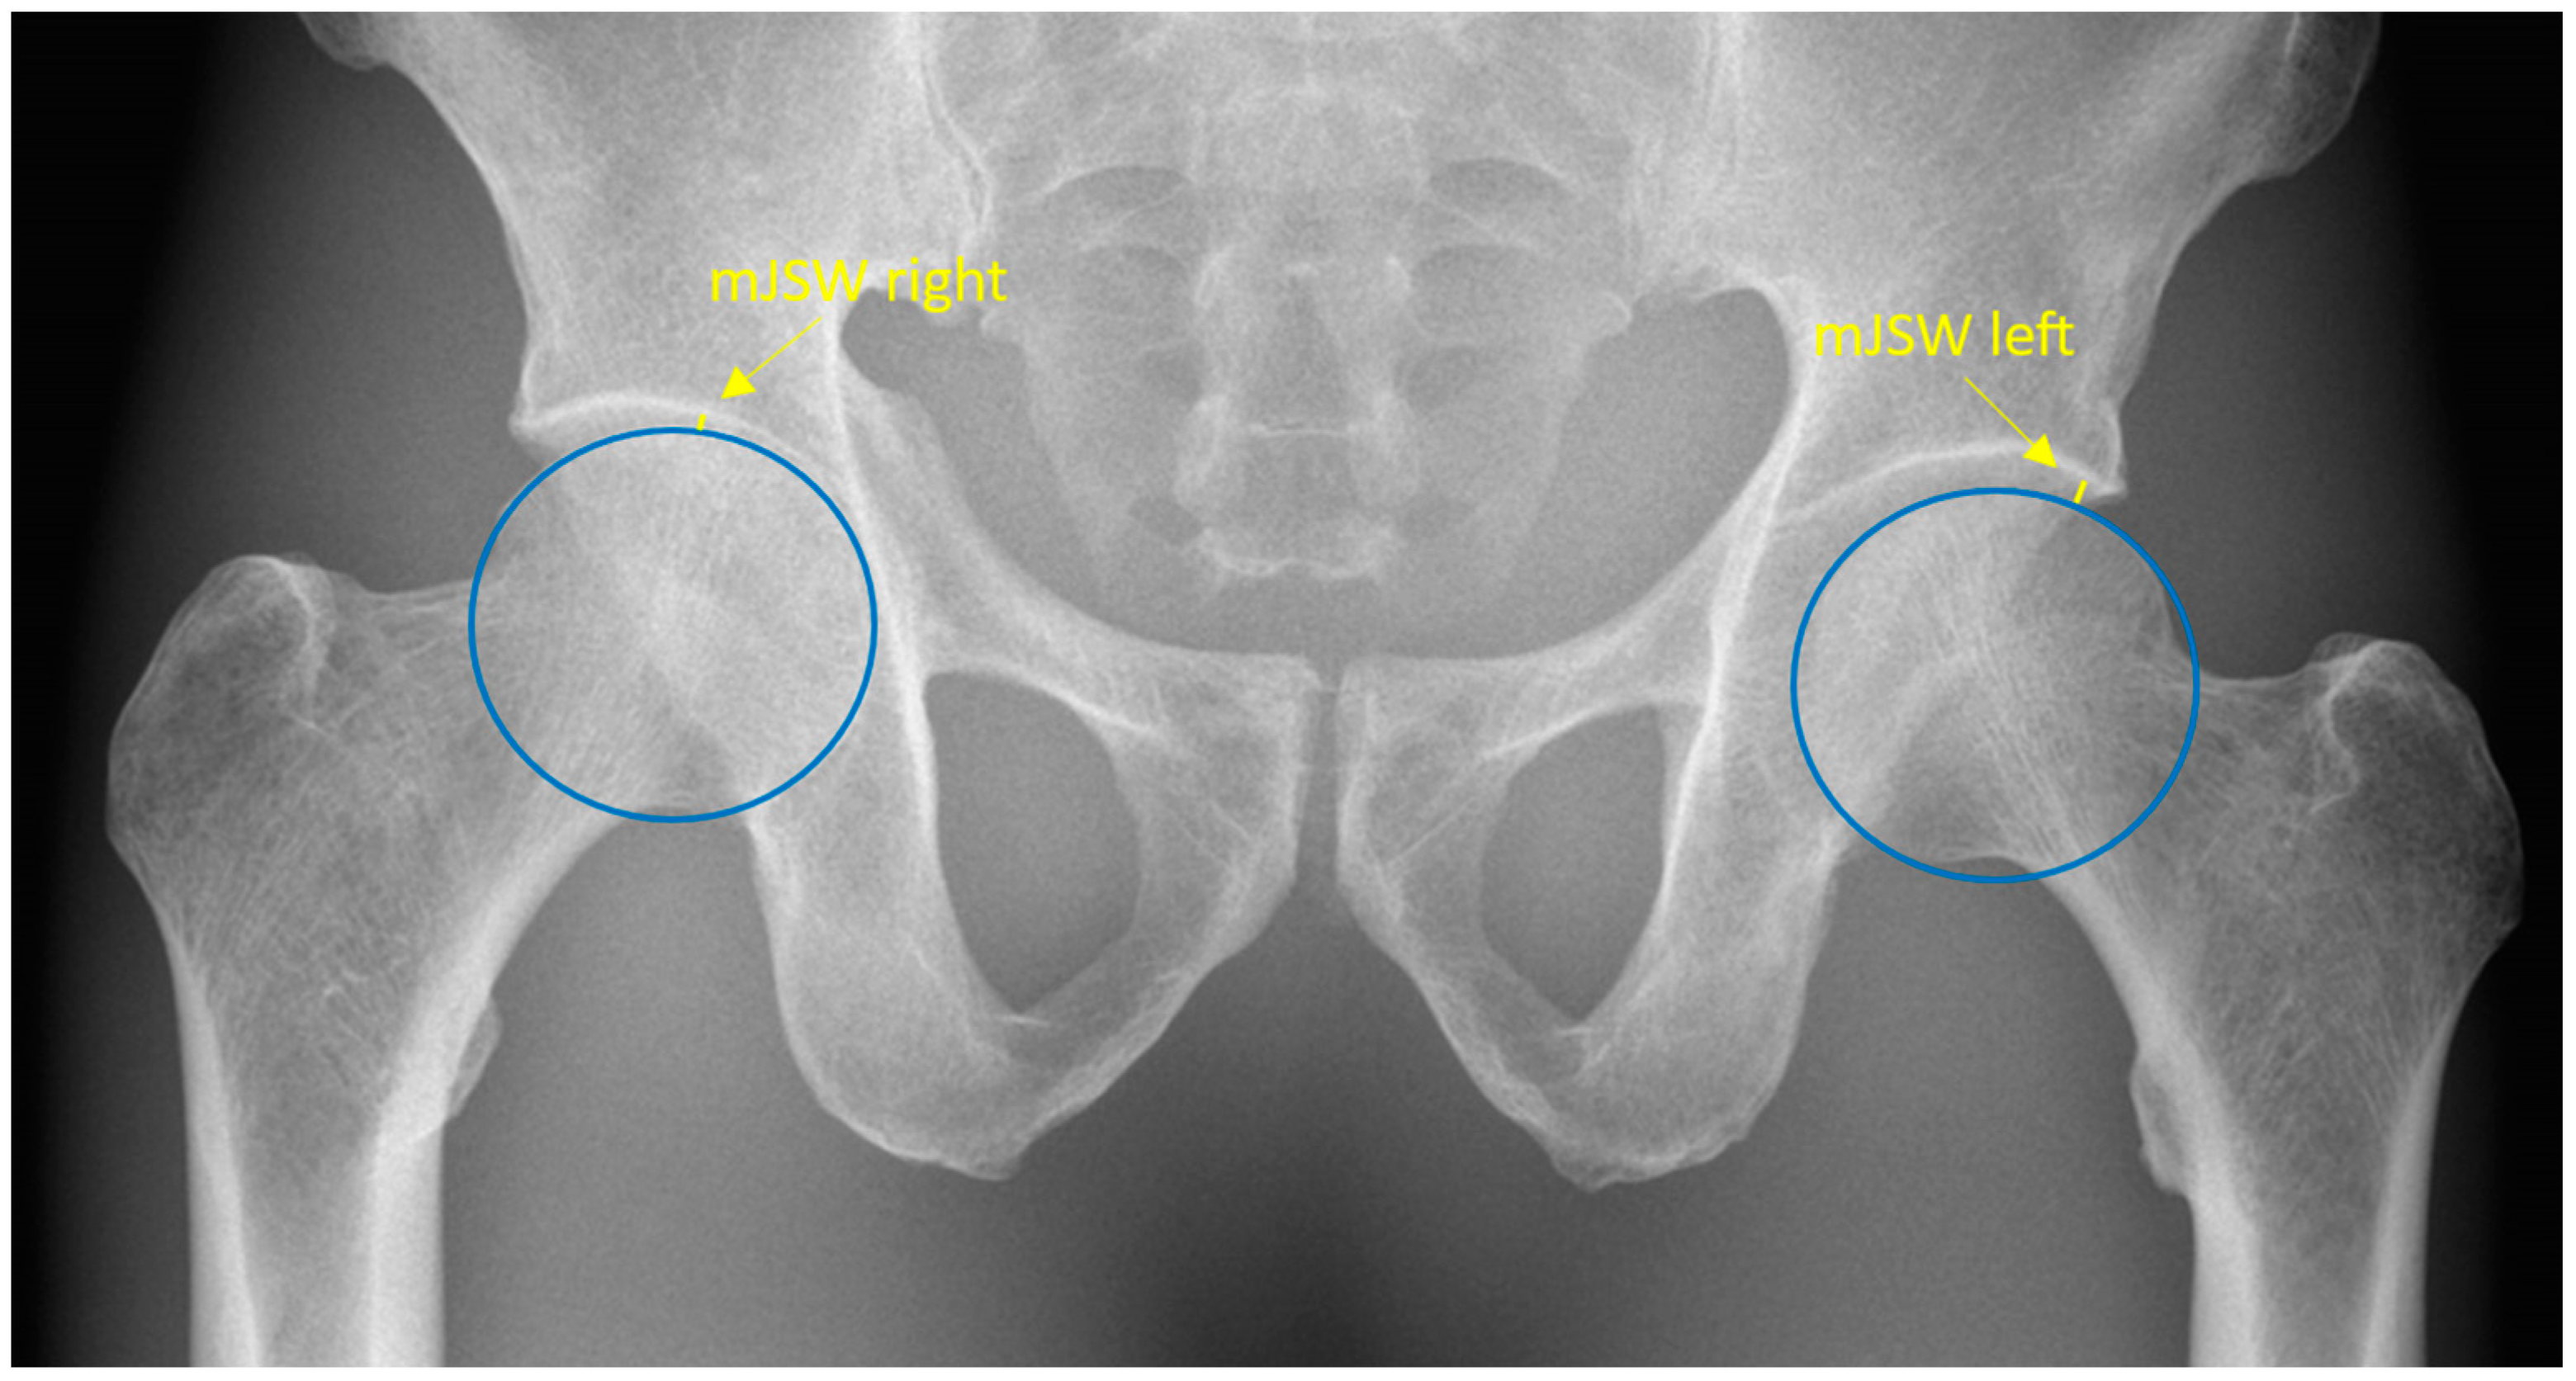

The mJSW is anatomically defined as the minimum width of the superolateral femoroacetabular joint space. Radiographically, the mJSW is defined as a line indicating the narrowest part of the superolateral aspect of the femoroacetabular joint, as shown in Figure 1. The superolateral aspect of the acetabulum is defined by the sclerotic sourcil, which refers to the weight-bearing, sclerotic surface of the acetabulum.

Figure 1.

Pelvic radiograph. The blue circles depict the two femoral heads. The yellow lines represent the minimal joint space width and are specified by the yellow arrows.